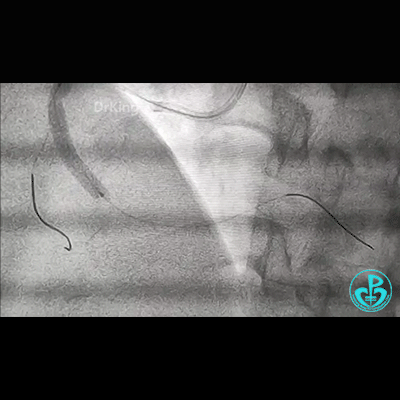

右锁骨下动脉迂曲打圈,影像如下:

导丝怎么扩右冠近段弥漫性病变中远段闭塞顺利开通并植入支架,哪知道故事才刚刚开始!!!_https://www.jmylbn.com_新闻资讯_第1张